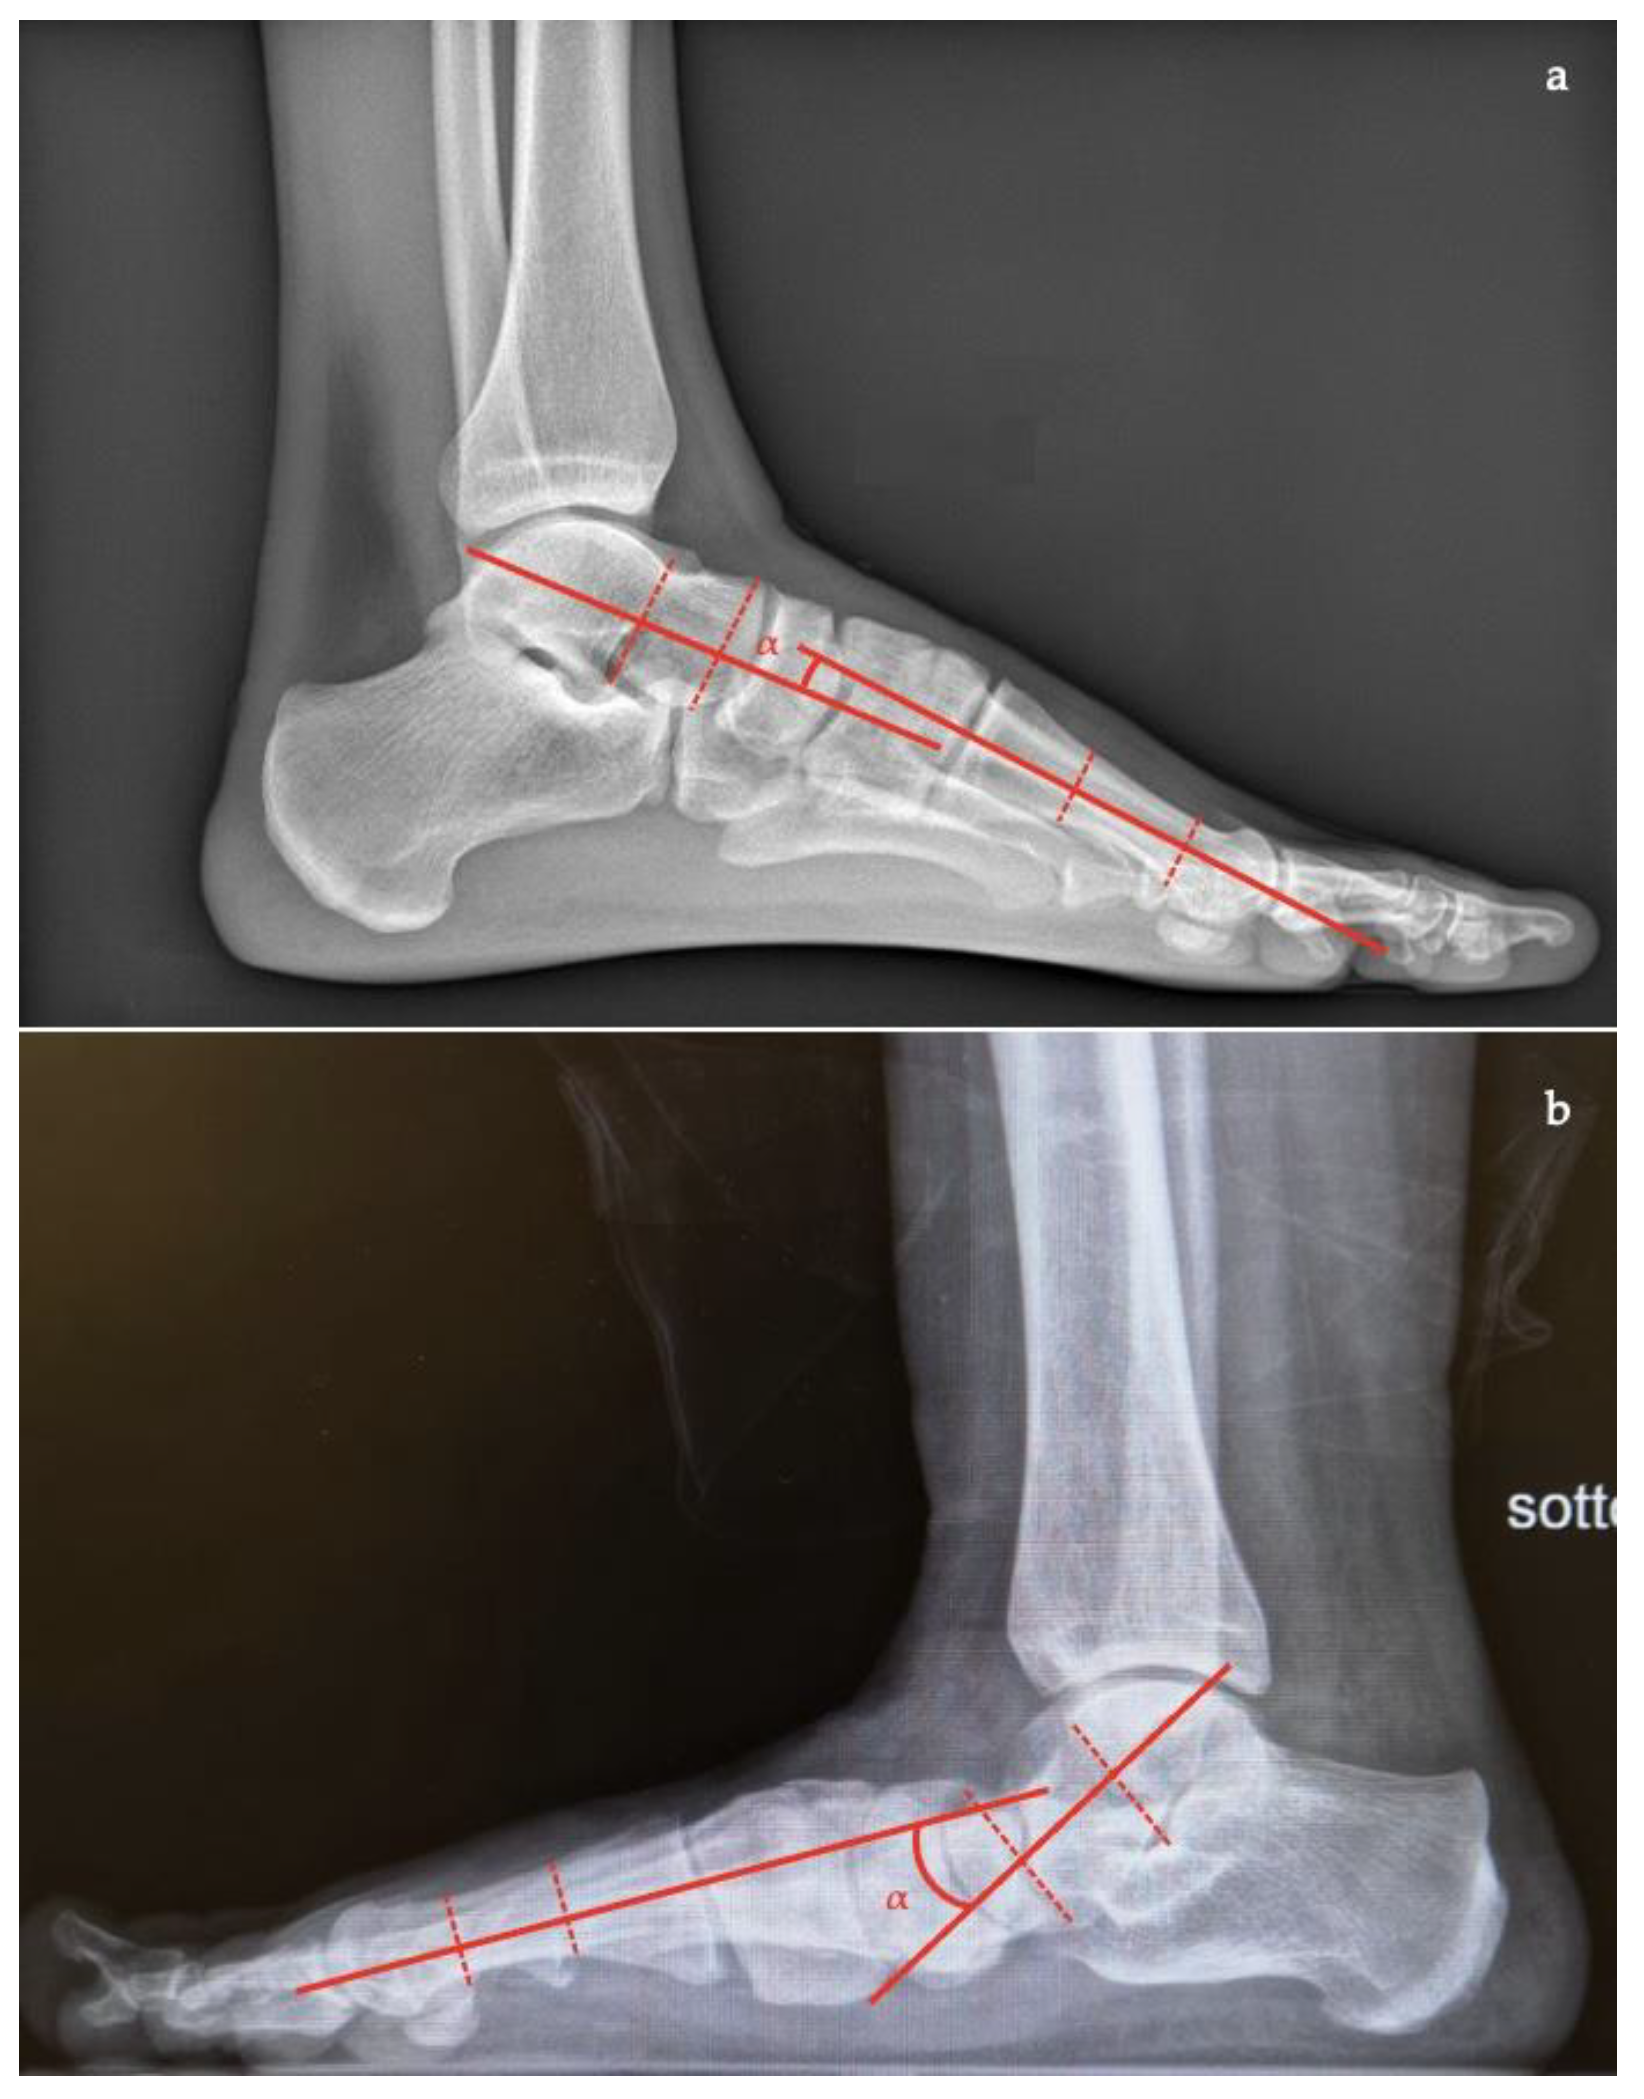

- Talar–first metatarsal angle, between the lines drawn along the long axis of the talus and the first metatarsal (normal 0°, flatfoot: mild >4°, moderate >15°, severe >30°) (Figure 1);

- Talar–first metatarsal angle (Meary’s angle), the normal value is 0 ± 10 degrees and is increased in flatfoot deformity (often >20°, apex directed plantarly) (Figure 5);

- Calcaneal pitch, the angle between the line parallel to the ground and the line along the inferior inclination axis of the calcaneus (normal, 20–30°; flatfoot, <20°) (Figure 6);

- Talocalcaneal angle is formed by the long axis of the rearfoot and the midtalar line. This angle is increased in pronated feet on both the AP and lateral views (normal <45°, flatfoot >45°) (Figure 7);

- Calcaneal-fifth metatarsal angle, defined as the angle formed between the tangent to the inferior aspect of the calcaneus and a line drawn along the inferior aspect of the base and head of the fifth metatarsal (normal <170°, flatfoot >170°) (Figure 8).